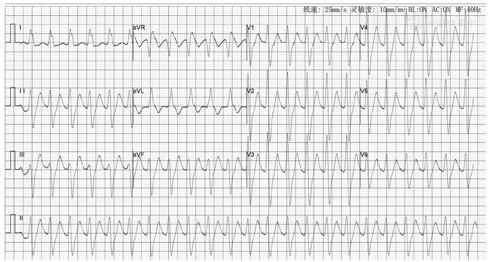

患者男性,19岁,因"自服阿米替林200片后意识不清2 h"于2019年1月30日被送入常德市第一人民医院急诊科。患者服药后出现意识不清、呼之不应,被发现时无抽搐、无口吐白沫,阿米替林每片25 mg,共服用5 g。患者既往有抑郁症,无其他特殊病史。查体:体温36.5 ℃,脉搏138次/min,呼吸20次/min,血压112/69 mmHg(1 mmHg=0.133 kPa),中度昏迷,瞳孔等大等圆约4 mm,对光反射灵敏。心率138次/min,节律整齐。脑膜刺激征阴性,双侧巴宾斯基征阴性。服药2.5 h ECG为宽QRS波(约160 ms)心动过速,报告:阵发性室性心动过速(图1)。诊断:(1)急性阿米替林中毒;(2)心律失常:室性心动过速。立即予以洗胃、血液灌流及血液滤过等处理,并分别予以双相100焦耳、150焦耳及200焦耳同步电复律共3次,均失败。患者服药10 h复查ECG仍为宽QRS波心动过速,但QRS波宽度缩窄为142 ms,且QRS波前可见清晰窦性P波,报告:窦性心动过速,不定型室内传导阻滞(图2)。患者服药20 h后复查ECG示QRS波形态恢复正常,QRS波宽度为114 ms,额面电轴+50°,报告:窦性心动过速(图3)。头部CT未见明显异常。肺部CT示双肺炎症,胸腔少量积液。患者服药24 h左右被送入重症监护室继续诊治,心肌酶、心肌肌钙蛋白正常。患者服药后30 h查ECG为窦性心动过速,QRS波宽度100 ms,额面电轴+66°。继续血液灌流、血液滤过、头部亚低温、促醒护脑、抑酸护胃、静滴碳酸氢钠及维持内环境平衡等治疗。2月1日患者可睁眼及四肢活动。24 h动态ECG、心脏彩色多普勒超声未见明显异常,头部MRI平扫及扩散加权成像均未见明显异常。

注:心率138次/min,QRS波宽度约160 ms,额面电轴-64°

本例患者服药后2.5 h ECG(图1)显示心率138次/min,QRS波宽度约160 ms,额面电轴-64°,符合第2项即V1或V2导联QRS波起始r波时限>40 ms,积分为1分,难以明确诊断,但电复律3次均无效,提示极有可能并不是室性心动过速。服药后10 h ECG(图2)中可见清晰窦性P波,心率111次/min,QRS波宽度约142 ms,额面电轴正常(+35°),符合窦性心动过速,不定型室内传导阻滞。比较图1、图2,除QRS宽度及额面电轴变化,其余特征大致相同,继续观察至服药后20 h ECG(图3)及30 h ECG,QRS波分别为114 ms和100 ms,额面电轴分别为+50°和+66°,提示随着室内传导阻滞逐渐改善,QRS波进行性缩窄,额面电轴进行性恢复。